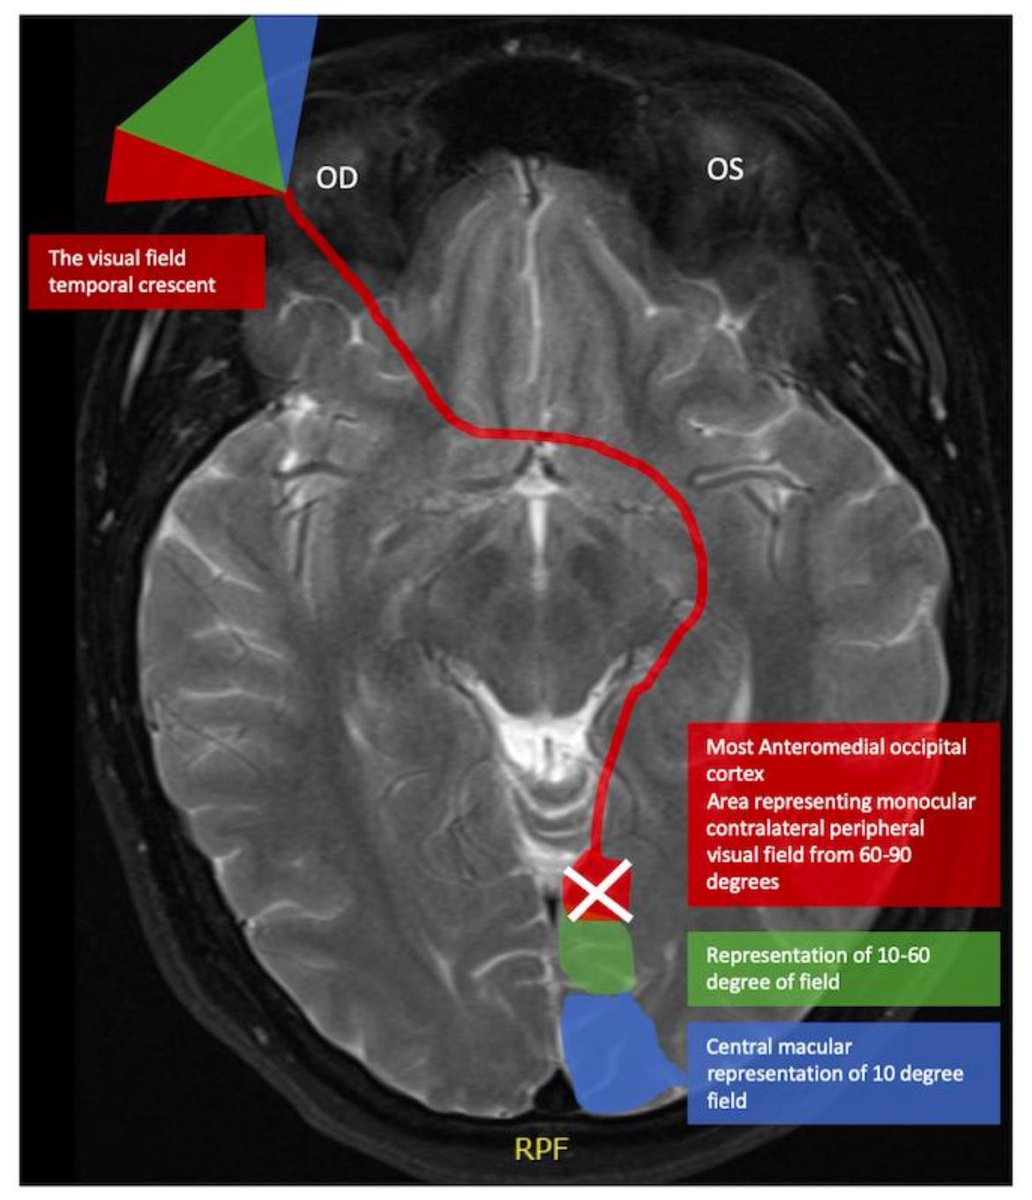

كل فص منهم له مهمته انه يعالج اشارات معينه و يعيد إرسالها، و اللي يهمنا في متلازمتنا اليوم آخر فص Occipital lobe اللي مسؤول عن معالجة اشارات العين

في متلازمة انتون يكون الفص متضرر سواء بضربه او بجلطه او ب التهاب شديد

العين تكون سليمه و ترسل اشارات سليمه لكن معاجلتها لا تتم، و للاسف يكون عندنا عمى يسمى بالعمى القشري Cortical blindness